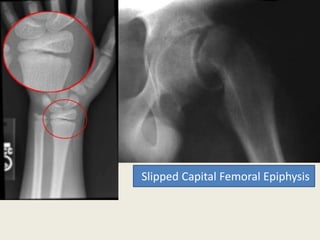

TypeI

Slipped Capital Femoral Epiphysis

• Approximately , half of all physeal injuries occur in the

lower end of the radius at the wrist .

• also occur frequently in lower bones ( tibia & fibula) also can

occur in femur .